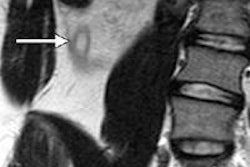

The group proposed the following imaging protocol: Patients presenting in the emergency department with right lower quadrant abdominal pain would receive an ultrasound first. If the ultrasound was positive, the patient would be sent for an appendectomy because ultrasound has a high positive predictive value for appendicitis.

However, if the ultrasound findings were negative or uncertain, patients would undergo a CT exam. If the CT findings were positive, they would have an appendectomy; if negative, no further treatment would be performed.